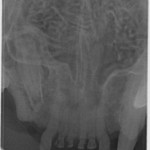

Tænder med TR skal trækkes ud. Men alligvel er det nødvendigt at tage tandrøntgen af alle tænderne for at se om der er andre tænder, der er angrebet af TR.

På Dyretandspecialist kan du læse mere om sygdommen Tooth Resorption (TR/FORL) hos katte. Her kan du både se røntgenbilleder og billeder af tandsygdommens stadier, samt se symptomerne på sygdommen, så du ved, hvad du skal være opmærksom på hos din kat.

Nedenfor kan du se de 8 røntgenbilleder af Shana-Mio´s tænder, som specialtanddyrlægen tog af hendes tænder i 2008, da hun fik konstateret TR/FORL: